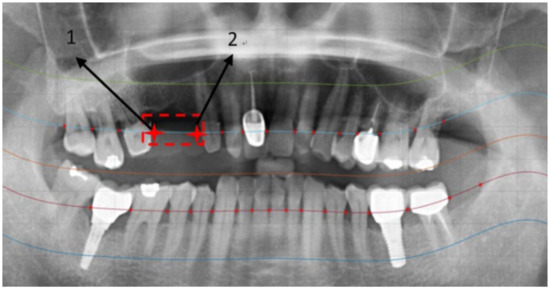

2.2. Image Segmentation

2.2.1. Curve of the Mouth

2.2.2. Curve Adjustment

2.2.3. Positioning Numbers

3. Results

| Positioning Accuracy Rate | ||

|---|---|---|

| Method in [26] | Our Method | |

| Positioning accuracy rate | 71.36% | 92.78% |